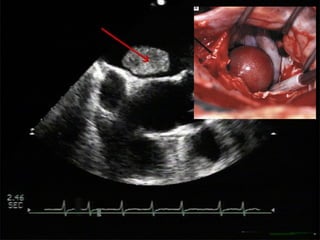

2. Unstable thrombotic mass

(transoesophageal echocardiography)

A transoesophageal view clearly shows a large

thrombus (red arrow) in the left auricle that may break

away at any moment.

3. Thrombus formation in the left auricle

(computer graphics superimposed on in-body

photograph)

The irregular beating of the heart in atrial fibrillation

creates ideal conditions for thrombus formation in the left

auricle, especially in patients with mitral valve

insufficiency.